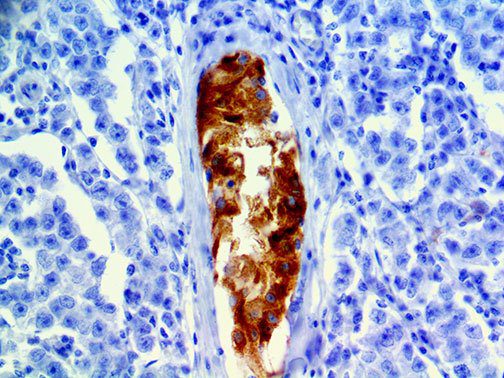

It is the ICU physician who is most likely to witness one of the deadliest manifestations of the abnormal immunological response, the cytokine storm syndrome (CSS). This response is also referred to by some as the cytokine release syndrome (CRS). CSS is characterized by continuous activation and expansion of macrophage and lymphocyte populations, which secrete large amounts of cytokines, causing the cytokine storm. This massive cytokine release is akin to hemophagocytic lymphohistiocytosis (HLH) disease, a syndrome characterized by initial unchecked and persistent activation of cytotoxic T lymphocytes and NK cells.

Clinical and laboratory manifestations of HLH include fever, enlarged liver and/or spleen, neurologic dysfunction, coagulopathy, liver dysfunction, cytopenias (i.e., low levels of erythrocytes, leukocytes, and/or platelets), hypertriglyceridemia, hyperferritinemia, hemophagocytosis, and eventually diminished NK cell activity as the immune system becomes progressively paralyzed. HLH can be familial (primary HLH) or secondary to another disease process (sHLH), such as rheumatic disease, in which it is referred to as macrophage activation syndrome (MAS, characterized by elevated ferritin).